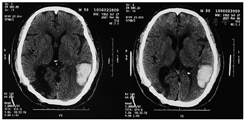

现病史:2021年3月6日再次出现头部不适,视力障碍,就诊于当地医院,头颅CT示"左颞枕叶脑出血"(图2),量约15 ml,予以降压等药物保守治疗,目前主要功能障碍为视野缺损、失读、失写、失计算、命名障碍、记忆力障碍等言语认知障碍。发病1个月后再次转入北京和睦家康复医院。入院评估,患者的主要功能障碍为手指失认、失读、失写、计算障碍、记忆障碍、时间定向力障碍,伴有经皮质感觉性失语。根据患者认知功能障碍、影像学特点,诊断为脑出血后古茨曼综合征。经过6周康复治疗,患者认知功能明显改善后出院。